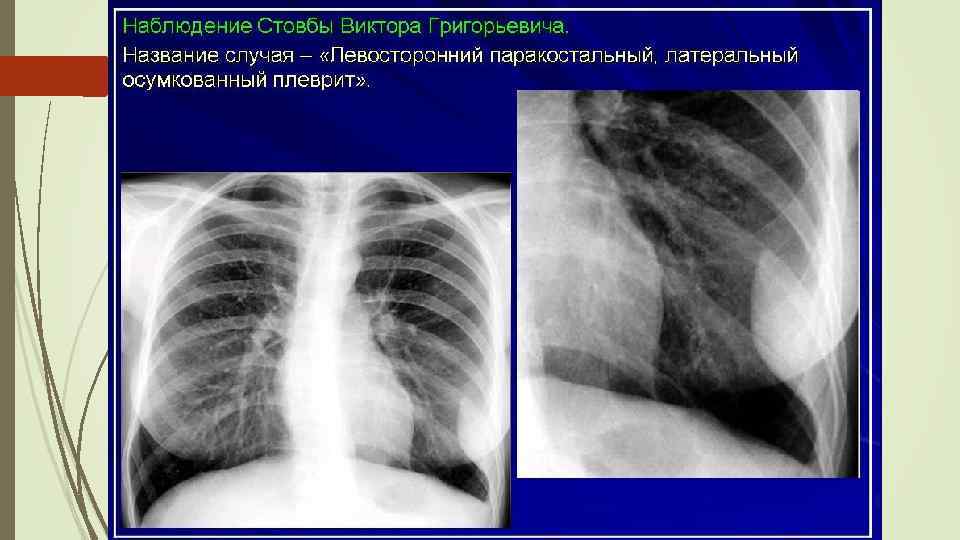

Осумкованные плевриты: а) пристеночные (паракостальные) осумкования, прилежащие широким основанием к поверхности ребер; б) верхушечные (апикальные) осумкования; в) диафрагмальные (базальные) осумкования, расположенные между основанием легкого и диафрагмой; г) междолевые (интерлобарные) осумкования, расположеные между долями легких; д) парамедиастинальные осумкования, расположенные в заворотах парамедиастинальной плевры.

Осумкованные плевриты: а) пристеночные (паракостальные) осумкования, прилежащие широким основанием к поверхности ребер; б) верхушечные (апикальные) осумкования; в) диафрагмальные (базальные) осумкования, расположенные между основанием легкого и диафрагмой; г) междолевые (интерлобарные) осумкования, расположеные между долями легких; д) парамедиастинальные осумкования, расположенные в заворотах парамедиастинальной плевры.